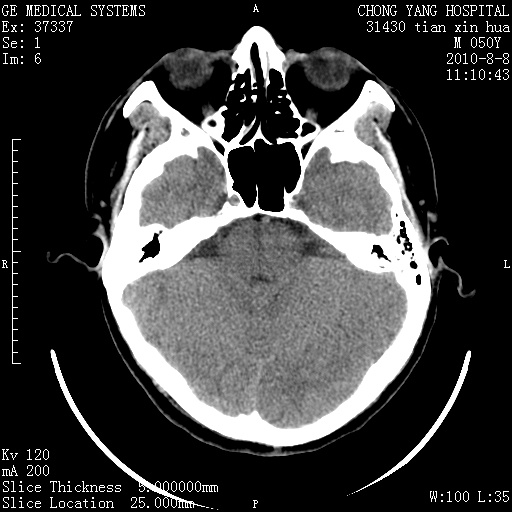

标题: CT28268:M50Y 头部外伤。 [打印本页]

标题: CT28268:M50Y 头部外伤。

考虑左侧枕部硬膜下积液。

乙状窦增宽,蛛网膜囊肿不除外

考虑左侧枕部蛛网膜囊肿;建议行mri检查。

病灶两端有脑膜尾征,考虑蛛网膜囊肿

枕骨稍变薄,脑组织有受压。首先考虑蛛网膜囊肿。